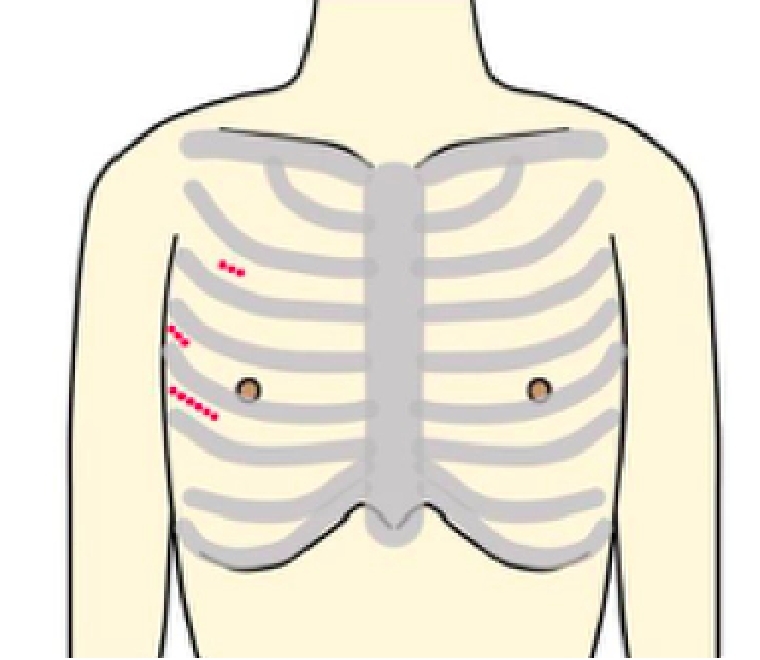

Minimally Invasive Cardiac Surgeryの略で、心臓低侵襲手術のことを意味します。

従来であれば胸骨という胸の真ん中を約20cm程切開しますが、MICSでは肋骨の間を3〜5cm程切開して行います。

当院では可能な方には3D内視鏡を用いた完全内視鏡下手術、及び傷が正面から目立ちにくい脇の下からの方法で、どちらも骨を切らず治療を行なっております。

生まれつき心臓の中の壁に穴が空いている心房中隔欠損症という病気に対しても、手術適応となる方には当院では完全内視鏡下に手術を行っております。僧帽弁の場合よりもさらに小さい傷で行う事が可能です。